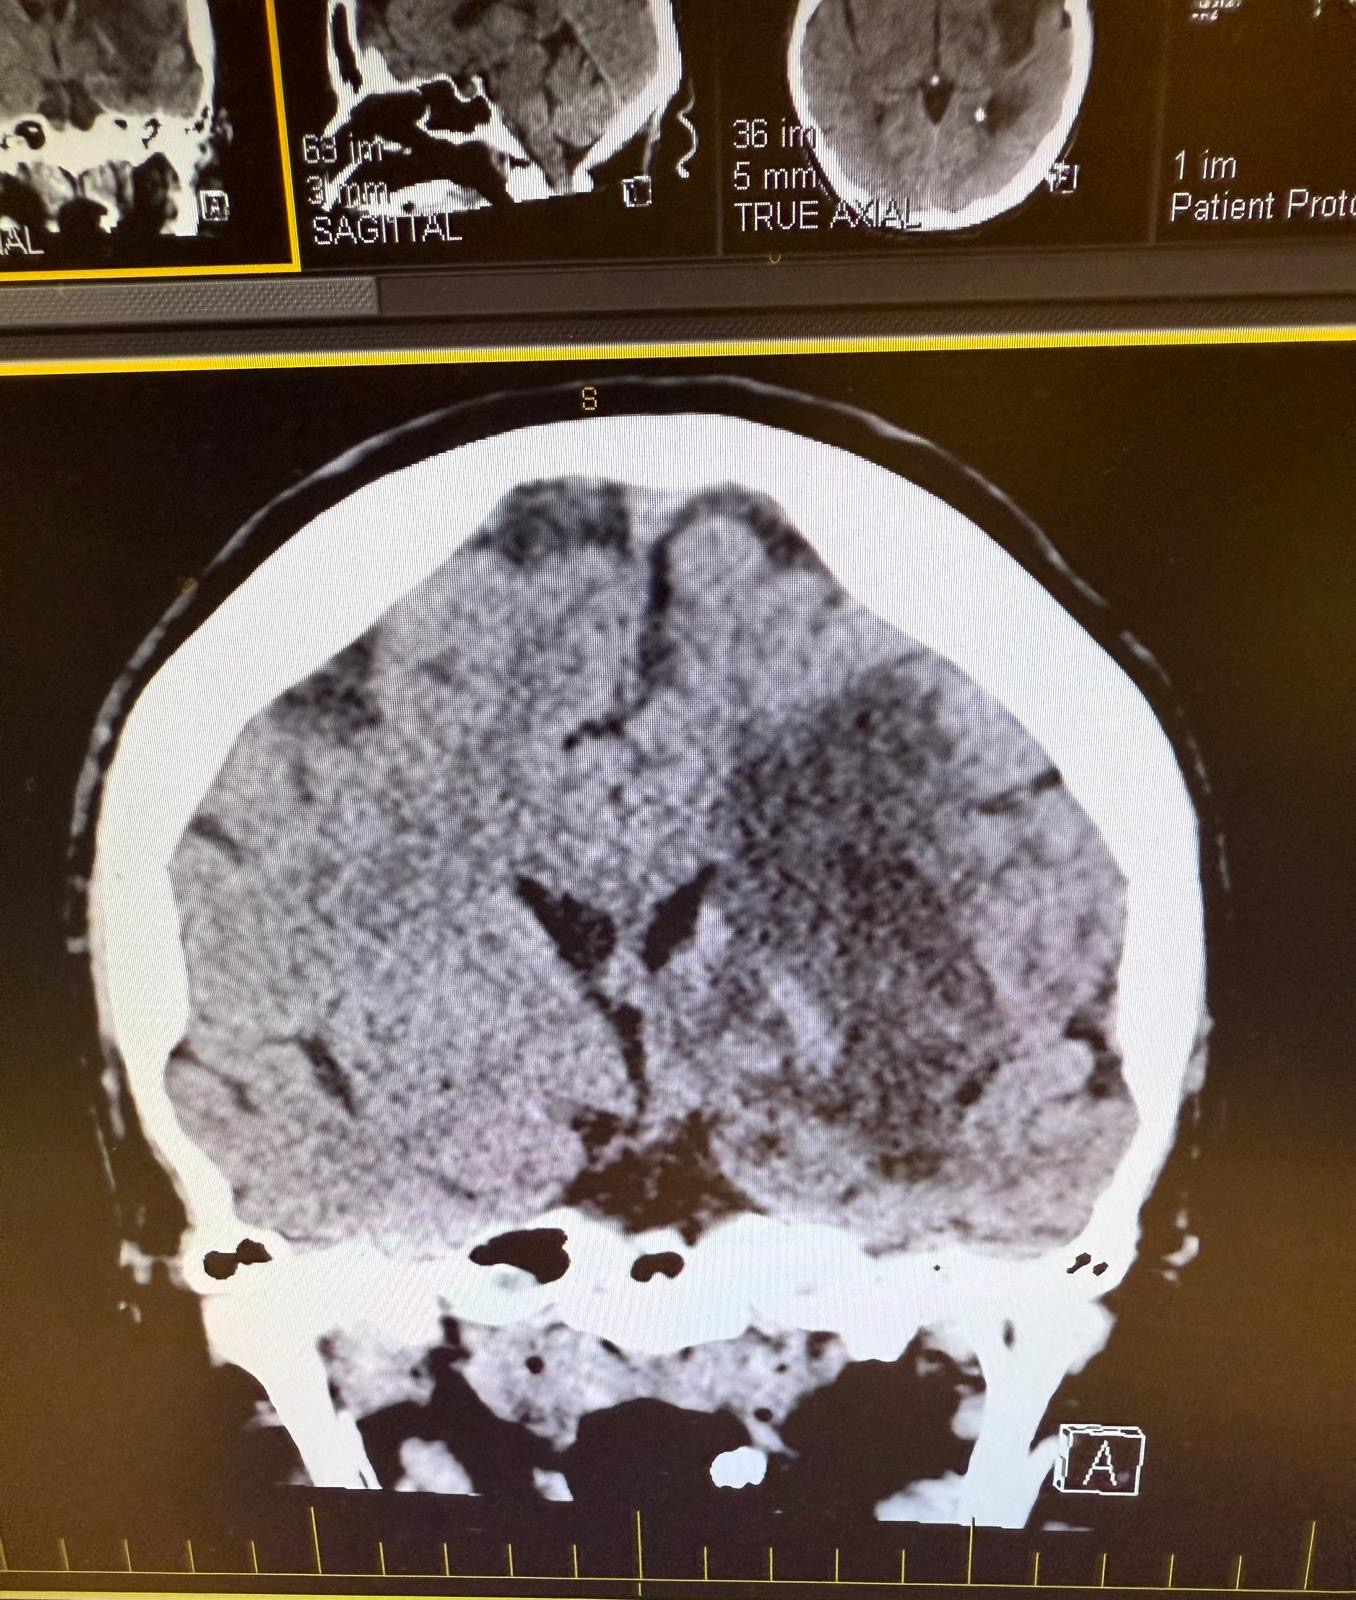

Our mom recently suffered multiple strokes but did not receive any medical care until her second stroke. She blamed her initial stroke symptoms on something else and didn’t want to get checked out due to lack of insurance. It wasn’t until the second stroke, after a whole day of symptoms, that she was finally taken to the emergency room.

She is now bedridden and unable to speak due to the strokes. She has zero mobility on her right side because of where the stroke was. It was devastating to see my mother in such a state. But we see her in there. Our mother understands everything we say and she shows us that she could get better little by little. The doctors say she’ll never be how she once was, but she shows willingness to get better, and today she showed signs of physical affection.